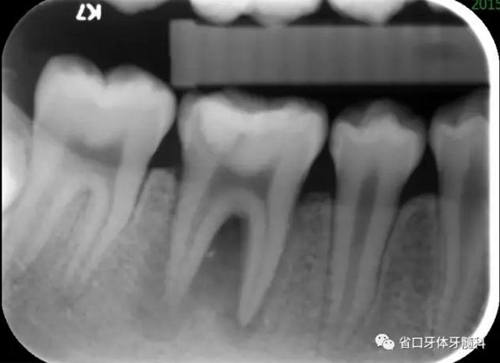

圖1 初診X片示根尖周及根分叉大范圍低密度影像